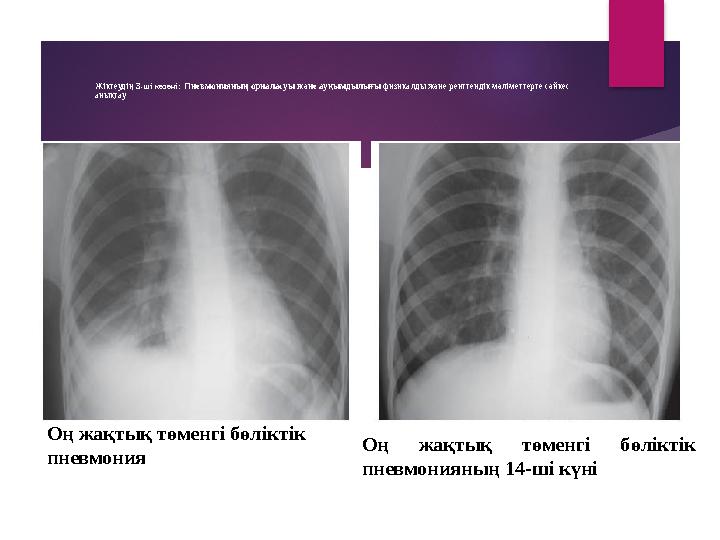

Жіктеудің 3 -ші кезеңі: Пневмонияның орналасуы және ауқымдылығы физикалды және рентгендік мәліметтерге сәйкес

анықтау

Оң жақтық төменгі бөліктік

пневмония Оң жақтық төменгі бөліктік

пневмонияның 14-ші күні